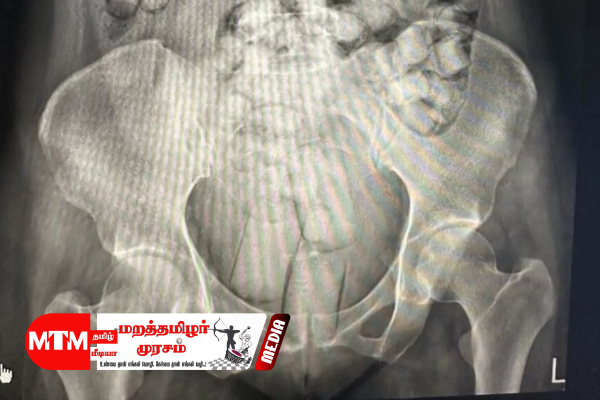

எக்ஸ்ரேயில் தெரிந்த அதிர்ச்சி காட்சி

அவர்களை எக்ஸ்ரே சோதனைக்குட்படுத்தியபோது, அவர்கள் உடலுக்குள் ஏராளமான கேப்சூல்கள் இருப்பது தெரியவந்துள்ளது.

ஒரு பெண்ணின் உடலுக்குள் 54 கேப்சூல்களும் மற்ற பெண்ணின் உடலுக்குள் 61 கேப்சூல்களும் இருந்துள்ளன.

அந்தப் பெண்கள் சிறிய அளவிலான கேப்சூல்களை விழுங்கியுள்ளார்கள். பெரிய கேப்சூல்களை அவர்கள் தங்கள் ஆசனவாய் வழியாகவும், சில கேப்சூல்களை பெண்ணுறுப்புக்குள்ளும் மறைத்து கொண்டுவந்துள்ளார்கள்.